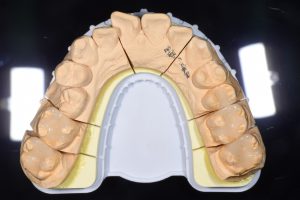

銀歯を全てセラミックにした症例

完成したセラミックインレー

治療後

この患者様の場合

1回目にカウンセリング

2回目に型取り

3回目にセラミックのセット

の合計3回で治療終了となりました。